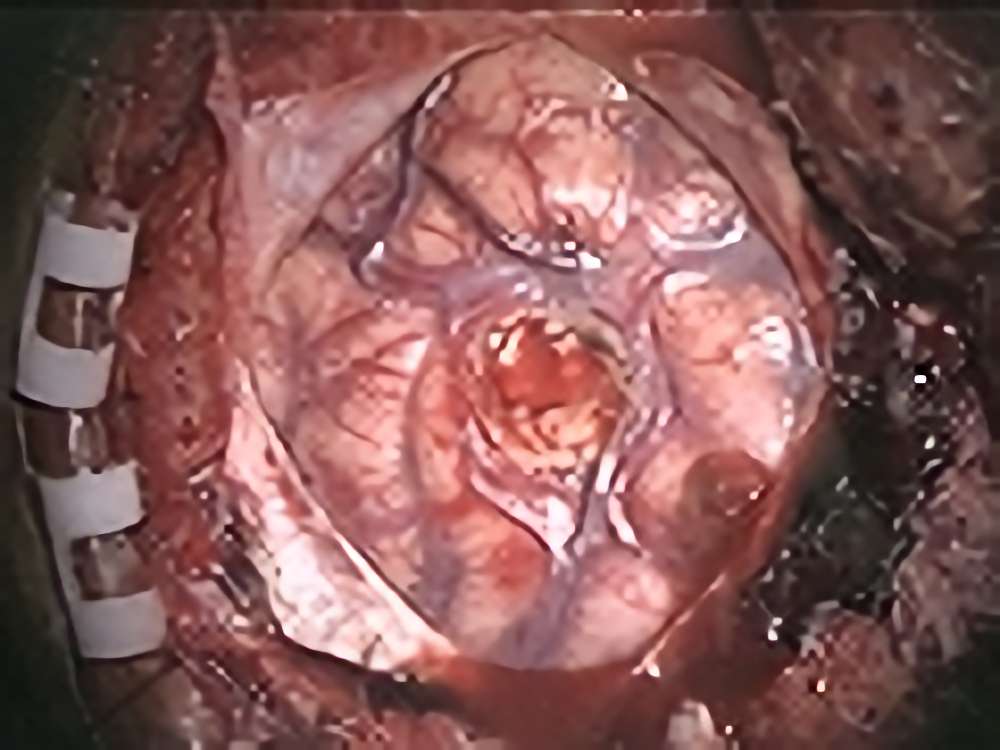

聴神経鞘腫

No.’14_1 手術前1

No.’14_1 摘出 前

No.’14_1 摘出 後